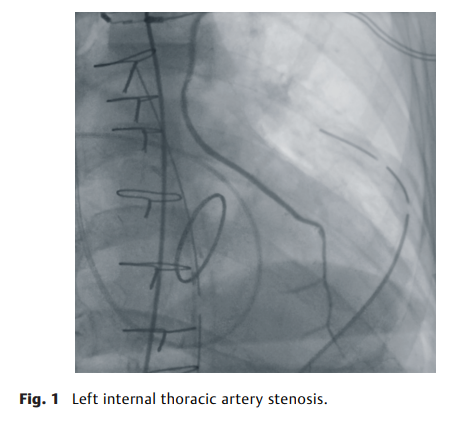

ICA 对3例患者(17%)的临床或手术决策有影响。在一名患者中,左胸内动脉 (LITA)的远端狭窄,因此进行双重抗血小板治疗6个月【图1】,两名 (11%) 患者进行了旁路移植物修复和额外的旁路移植术,这是由于一名患者的隐静脉移植物到钝缘支2阻塞【图2】,另一名患者有明显的 T 型移植物狭窄和移植物到左前降支阻塞【图3】。LITA。在这3例患者中,相应的外科医生认为ICA都优于TTFM。【图4】展示了令人满意的T型移植物血管造影。

图1. 左胸内动脉狭窄。